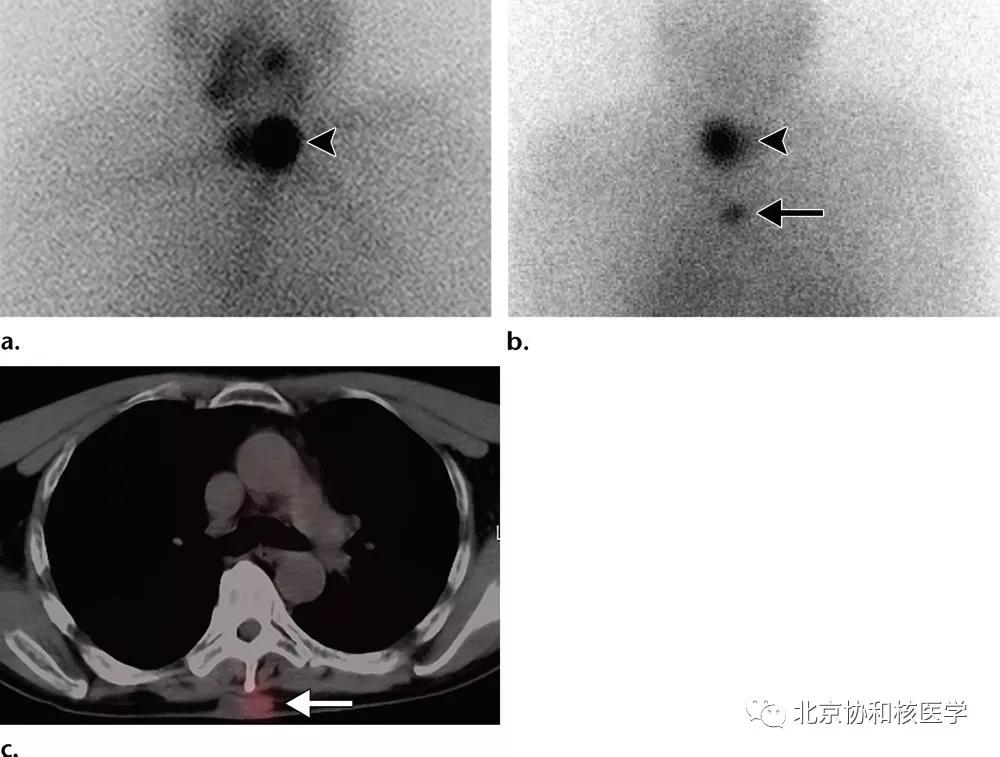

63岁女性,甲状腺癌病史,肺内不典型分支杆菌感染所致碘摄取:

肺内曲霉菌球摄取:

肺鳞癌所致碘摄取(后位图像),同时可见颈部甲状腺残余病灶: